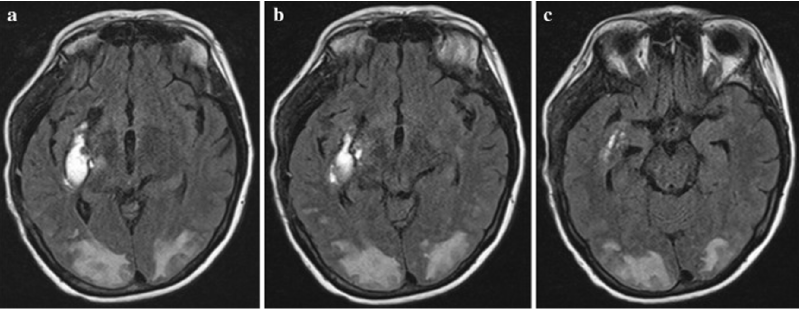

Nephrotic Syndrome and Posterior Reversible Encephalopathy Syndrome

Mohammed Qasem Masmali, Mohammed Ahmed Mohammed Wasili and Ahmed Ali Ahmed Jaafari. 5(10): 81-85.